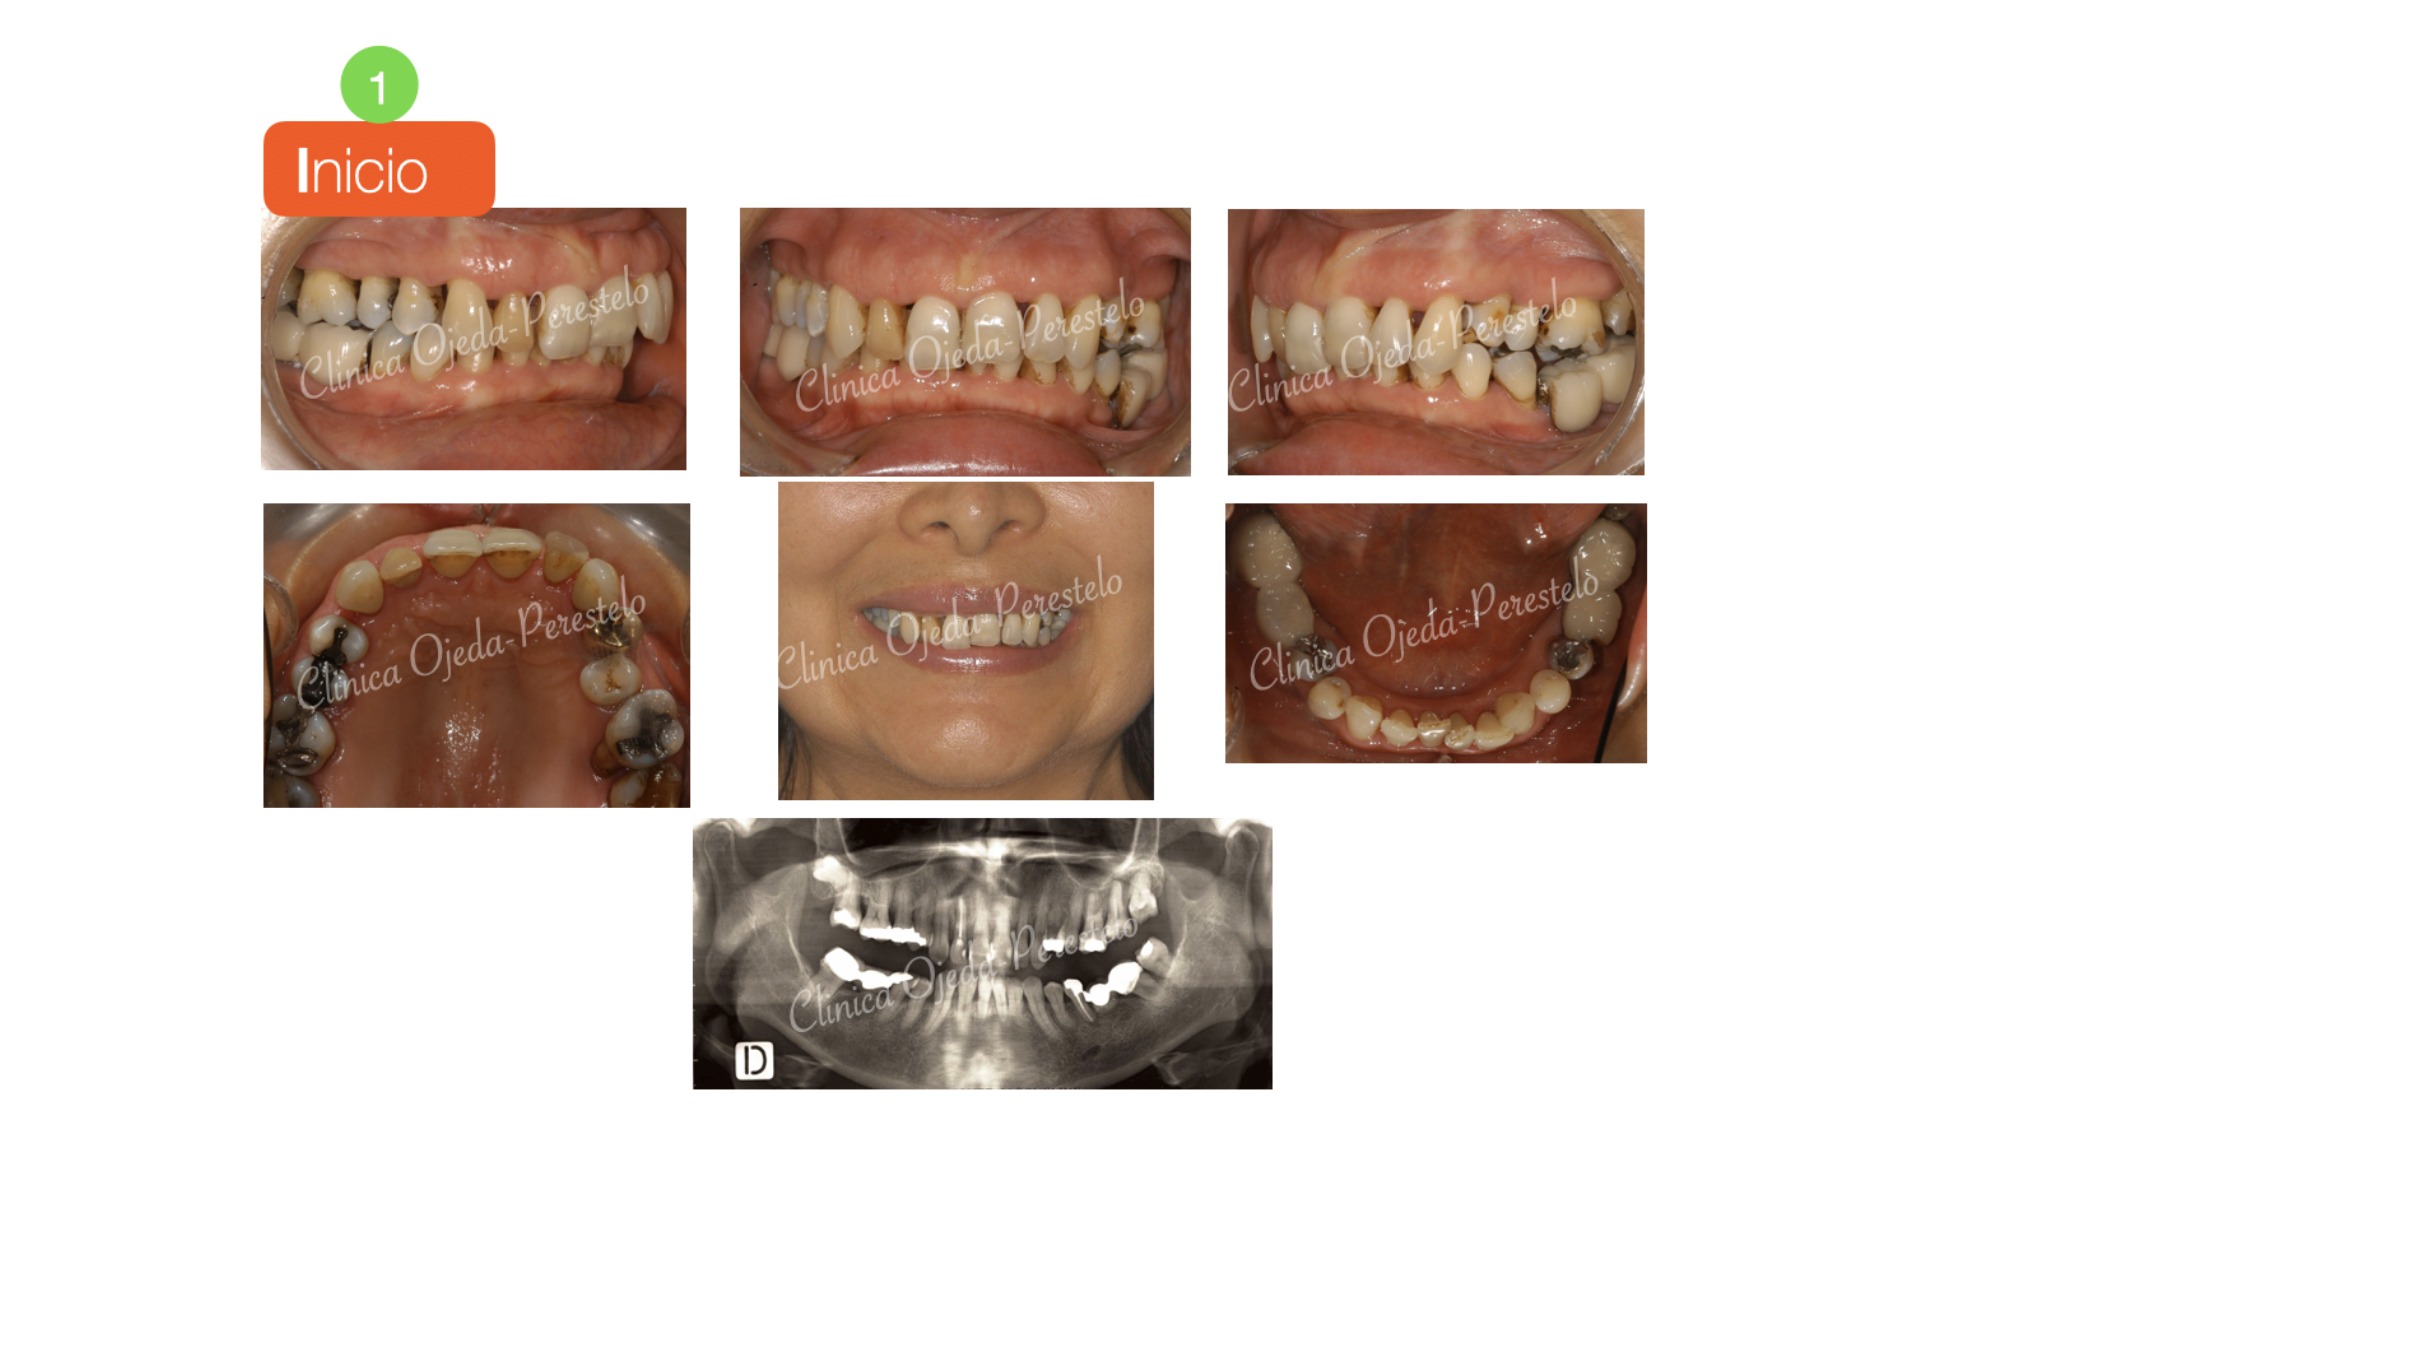

Caso Multidisciplinar: Ortodoncia-Implantes-Pónticos-Bioestética

La rehabilitación oral completa en los pacientes adultos requiere en algunas ocasiones de planes de tratamiento bien coordinados entre las diferentes disciplinas odontológicas. Presentamos un caso que tras la fase de higienización periodontal, comenzó su tratamiento de Ortodoncia con brackets. El objetivo de la etapa ortodóncica no era otro que alinear y nivelar sus arcadas dentarias en todas aquellas piezas con soporte radicular y adecuar los espacios para la colocación (futura) de implantes y pónticos. Al tratatarse de una paciente con enfermedad periodontal y pérdida ósea es crítico implementar un sistema de fuerzas ortodóncias leves (Sistema Damon). La paciente ha de  acudir a sus controles periodontales cada 4 meses durante la fase ortodóncica. (Dr Andrés García)

Una vez finalizada la fase ortodóncica comenzamos con la colocación de sus implantes y pónticos. La última etapa de este tratamiento interdisciplinar consistió en la colocación de carillas de porcelana en el sector anterosuperior (Bioestética) a excepción de la pieza 12 donde colocamos una corona de porcelana. (Dra Sara Stankova)

Queremos destacar la gran mejoría en la sonrisa en este caso de rehabilitación oral de alta complejidad donde 5 disciplinas odontológicas han estado sabiamente coordinadas. Creemos que solo de esta manera podemos conseguir este gran impacto estético-facial.